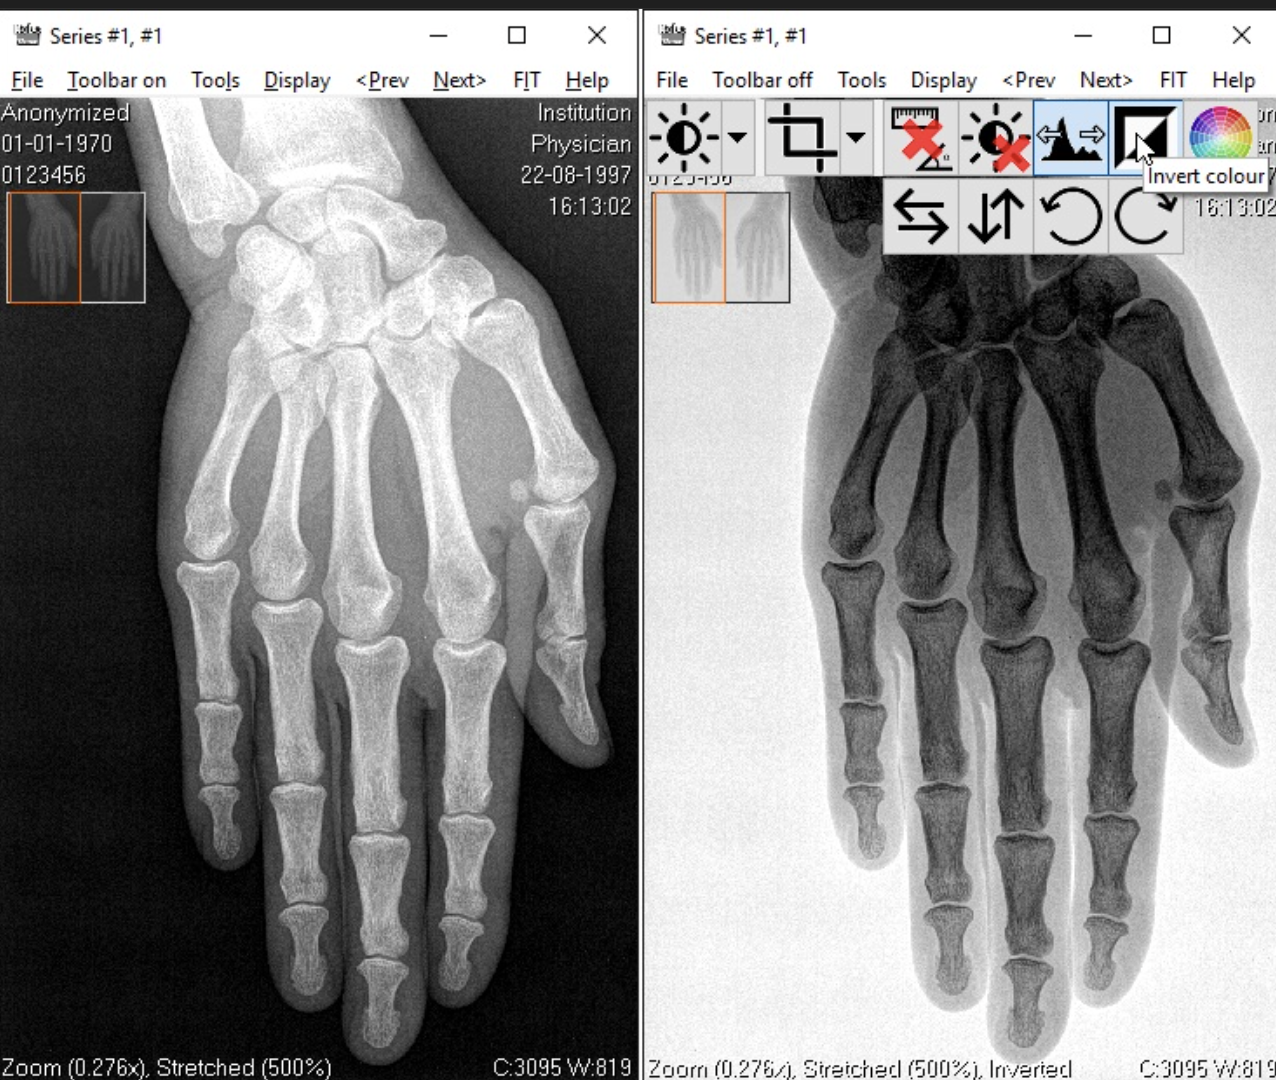

When is the inversion of gray scale tool used in radiograph processing?

Can be useful for endo and visualizing the pulp chamber.